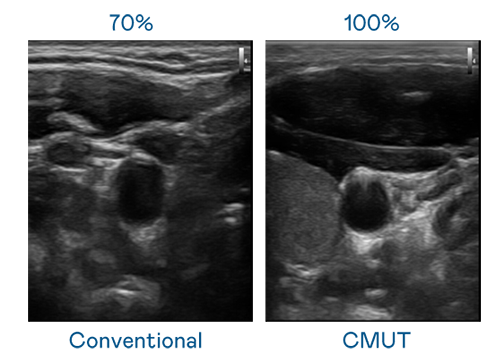

CMUT 技术是一种用电容式微机电元件来产生超音波讯号的技术。与传统 PZT 压电式技术相比,CMUT 频宽增加 30%,更宽频的超音波讯号让影像解析度大幅提升,是实现高影像品质医疗超音波扫描、促进精准医疗发展的关键技术。

超音波影像的解析度高低,首先取决于探头能发出的讯号频宽。BC贷 CMUT 可提供高清晰的超音波讯号,提供高频宽、高灵敏度、影像纹理细节更高的超音波影像,协助医护人员缩短影像判读时间及利用精准的医疗影像进行诊断。